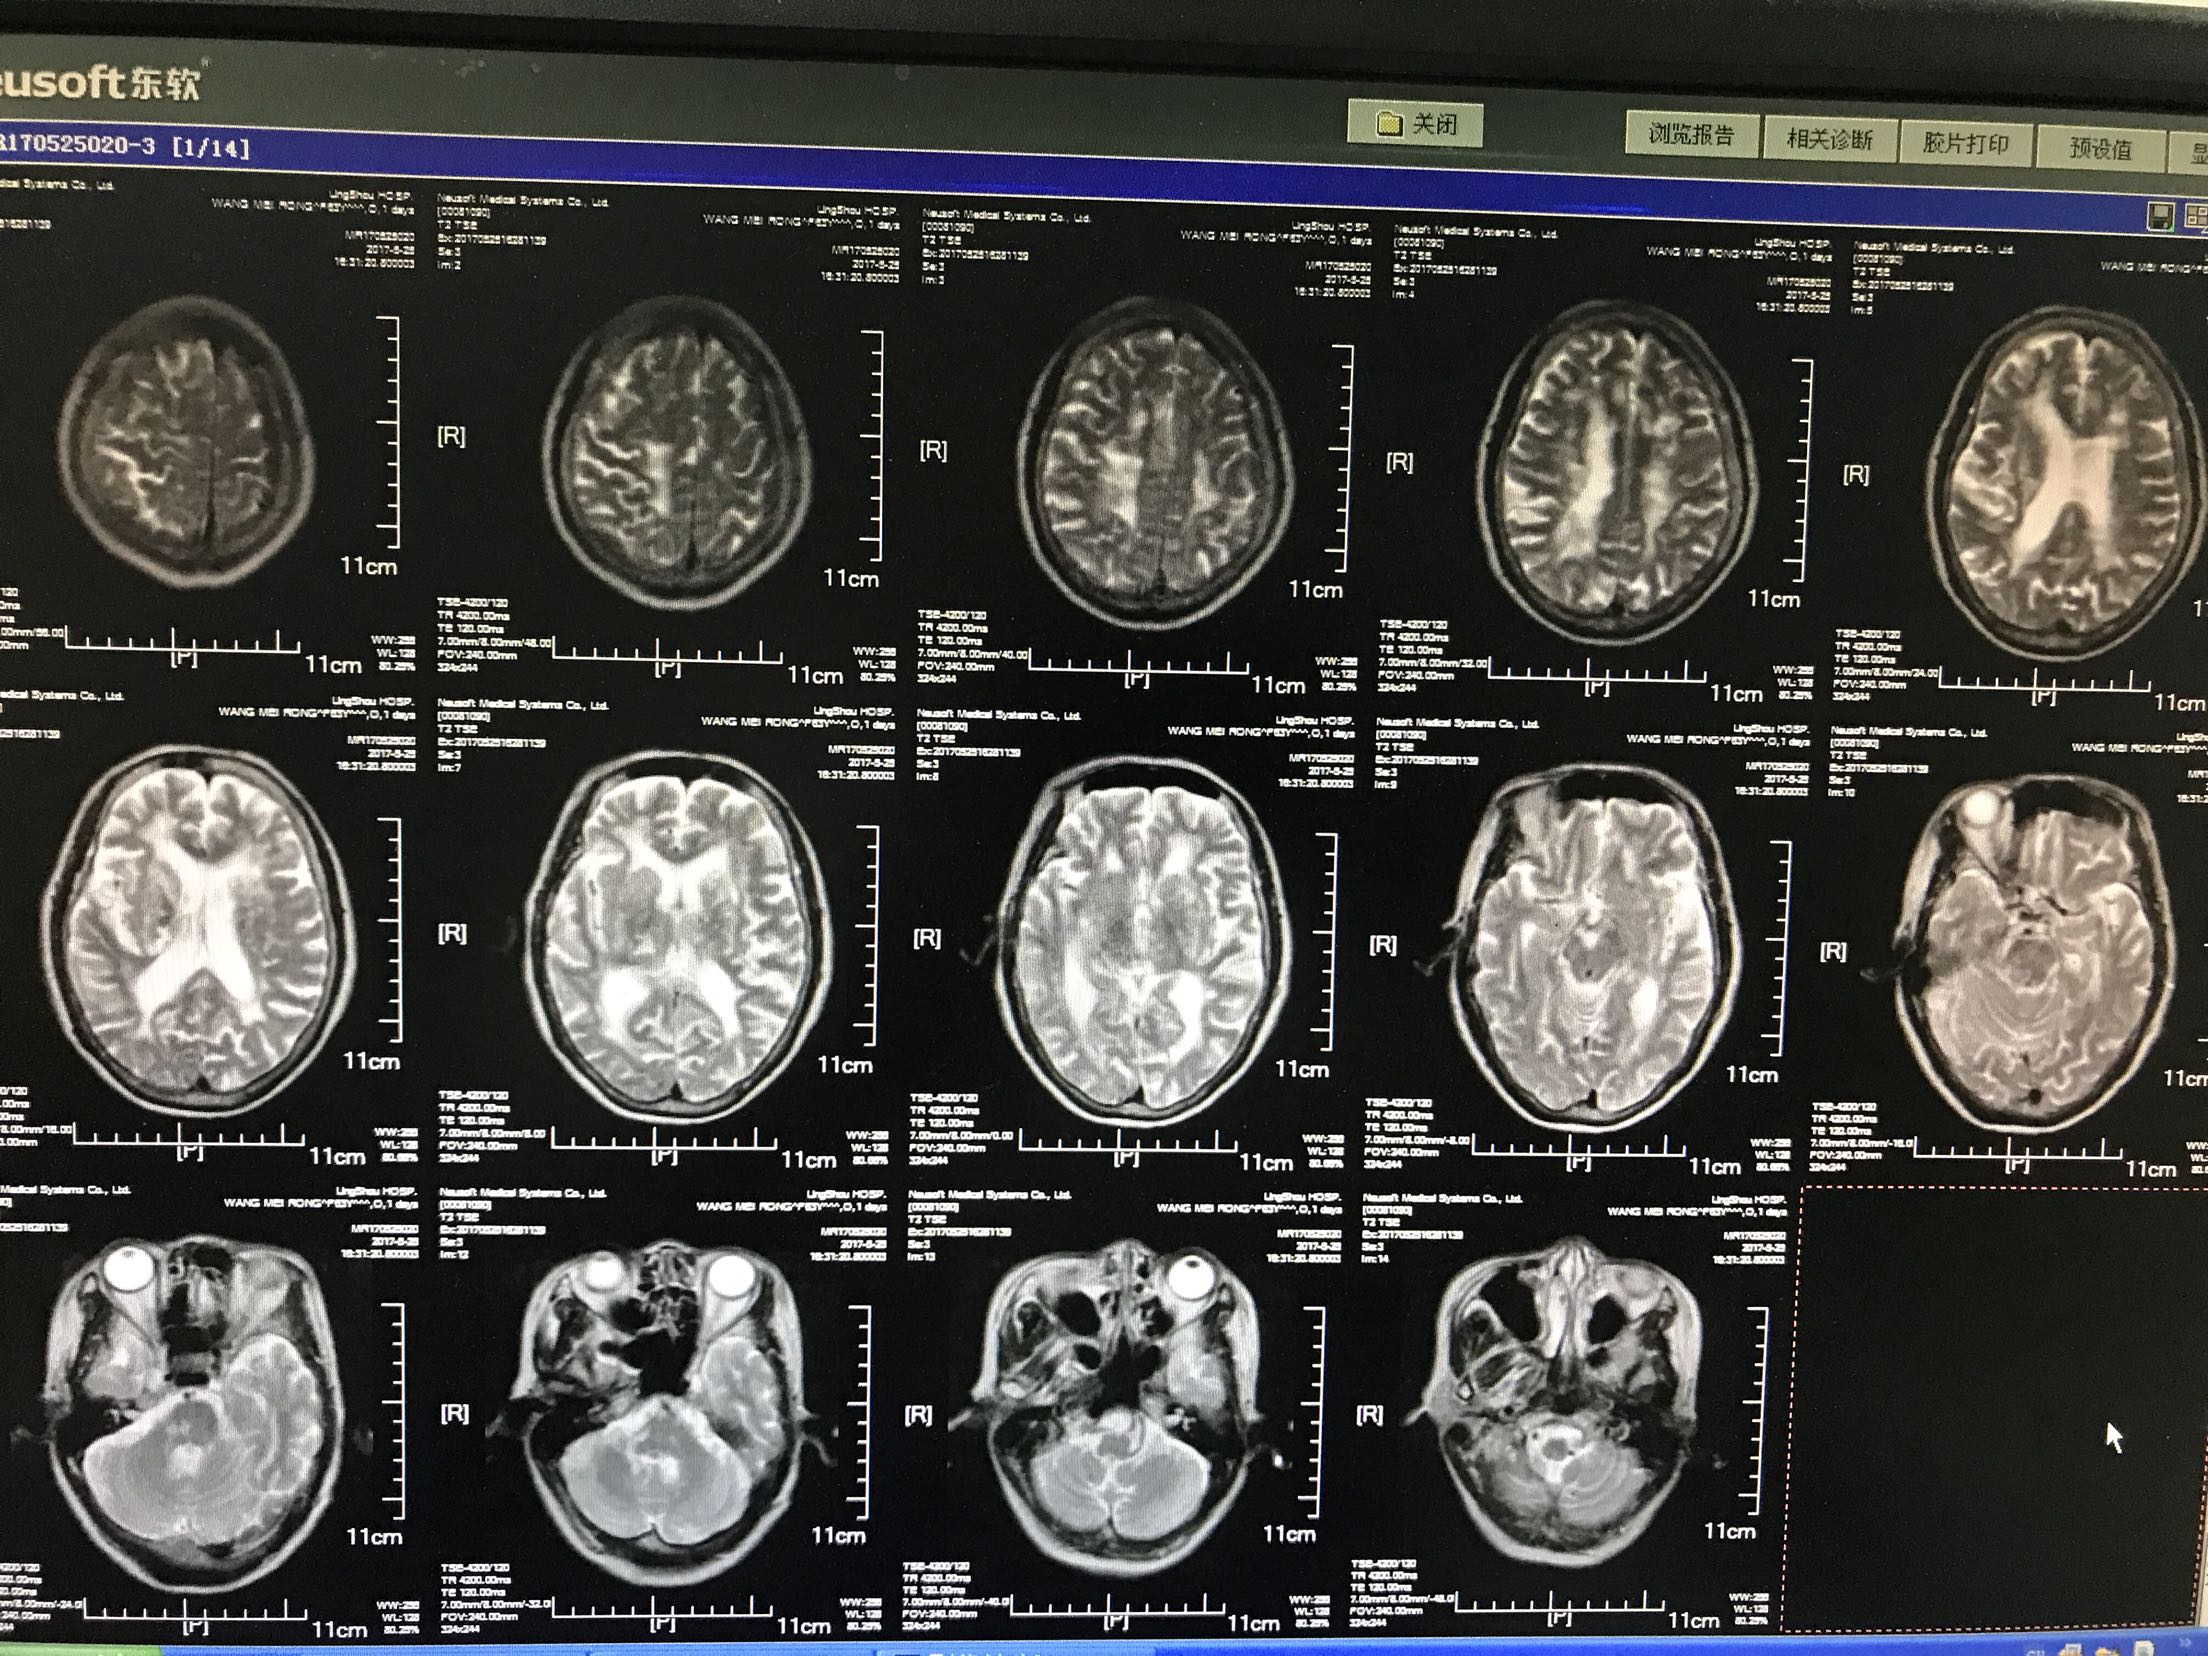

左侧肢体无力加重4小时入院,患者老年女性64岁,既往脑梗死病史10年,长期口服"阿司匹林",曾服用阿托伐他汀,后自行停服!留有左侧肢体无力后遗症,"糖尿病病史"5年,平素不规律服用"二甲双胍缓释片和消渴丸"。自诉血糖控制不佳,有夜间发生低血糖!"高血压"病史5年,长期口服氨氯地平片,具体血压控制不详。患者4小时前无明显诱因出现。左侧肢体无力加重,左上肢可以抬举持物,左下肢尚可负重,能独立行走,急诊查核磁示"脑梗死",收住院

体温37.5℃脉搏95次/分,呼吸22次/分,血压135/87mmhg,神情,言语基本流利,眼动充分,无明显眼震,伸舌居中,颈无抵抗,双肺呼吸音清,未闻及干湿性啰音,心音低钝,心律规整,未闻及杂音,双上肢肌力3级,肌张力增高,左上肢屈曲,双下肢肌力2级肌张力了,左巴氏征阳性,右巴氏征阴性,克氏征阴性,

1.脑梗死2.2型糖尿病3.高血压4.脑梗死后遗症,给于阿司匹林及波立维抑制血小板聚集,短效胰岛素控制血糖,阿乐稳定动脉板块,低分子肝素钙抗凝,降纤酶及脑苷肌肽等静点